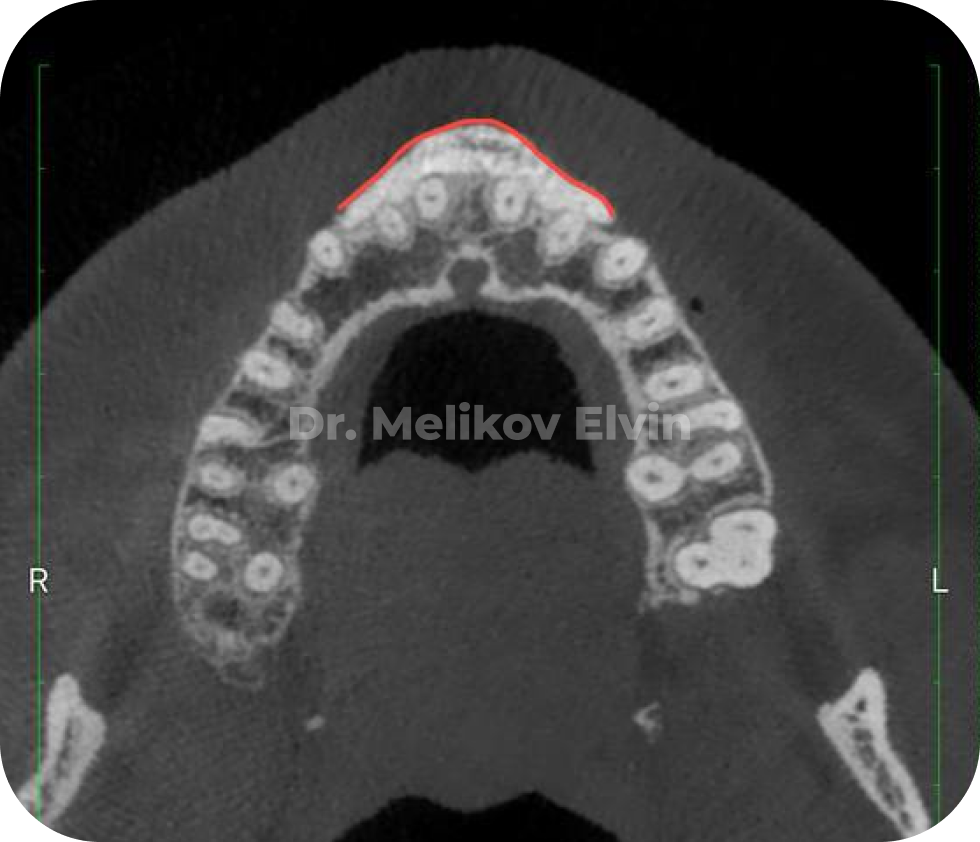

На снимках можно увидеть воссозданный объём наружной кортикальной пластинки в проекции корней зубов.

После костной пластики на верхней челюсти